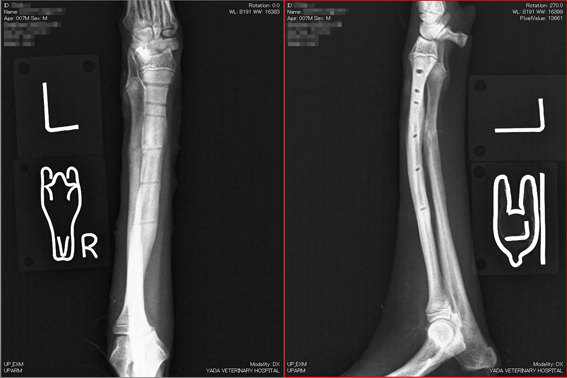

整形外科 骨 折 超小型犬の橈尺骨骨折(前肢)

当院では、側方刺入ピンによる創外固定法を施術しています、

全例で、癒合に導けています。

左橈尺骨遠位の骨折。

写真上段: 手術前

写真1段目: 手術前